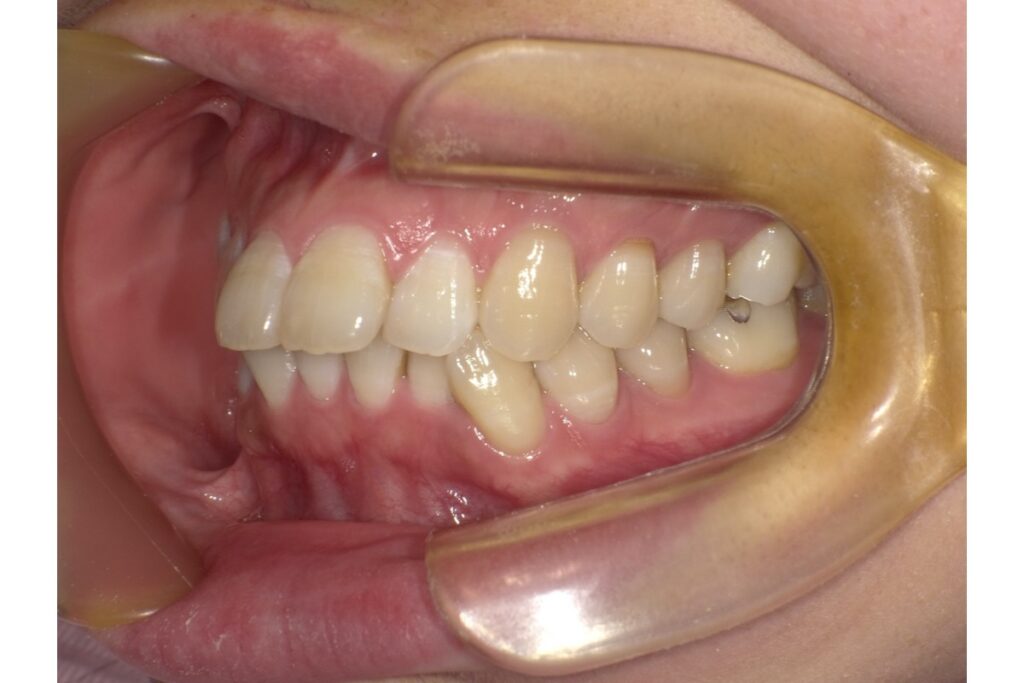

治療前

治療後

左下5番目の歯の治療前後の歯ぐきの位置を比較すると、歯茎が下がっているのがわかります。